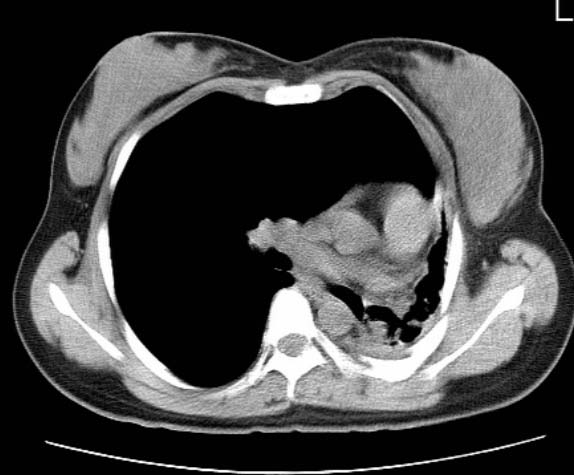

女  20岁。一月前咳血,诊“肺结核”抗痨治疗一月后,咳血停止,现复查。病人精神好。前后ct片对比未见明显变化。既往体检“正常”

1)考虑左肺结核并肺不张、支气管扩张。2)纵隔疝。

考虑左肺结核,左肺毁损,纵膈左偏,既往体检正常不可靠,tb一个月也不会这个样子的,有钙化,应该病程较长,冰冻三尺非一日之寒!

左肺发育不全。

考虑左肺结核,左肺毁损,纵膈左偏,既往体检正常不可靠,tb一个月也不会这个样子的,有钙化,应该病程较长,冰冻三尺非一日之寒

结核,左肺毁损。